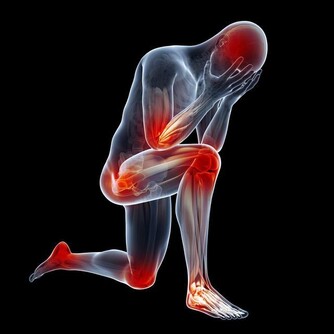

國外科學家研究發現,鎂可激活325個酶系統,把鎂稱為“生命活動的激活劑”是當之無愧的,而且,鎂對人的心臟血管具有重要的保護作用,人體如果缺鎂,就會導致心跳過速、心律不齊以及心肌壞死和鈣化等種種健康問題。

但問題是,在運動後和高溫條件下,特別是長時間、高強度運動,會大量消耗體內的鎂

,從而讓血清中的鎂明顯下降,降低肌肉的活動功能,甚至還會發生抽搐、痙等。